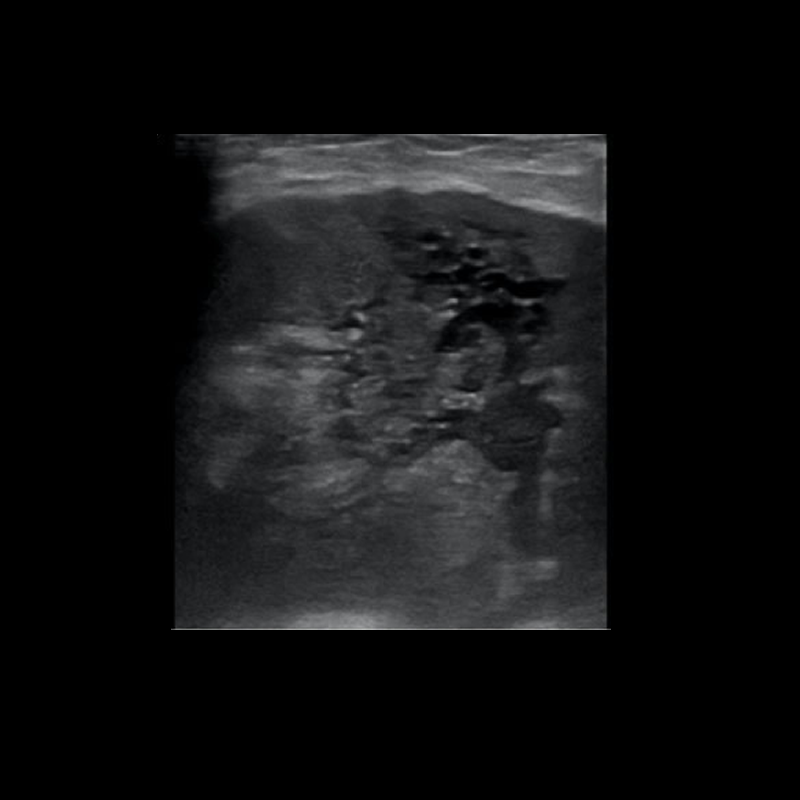

Paciente con masa palpable en mama